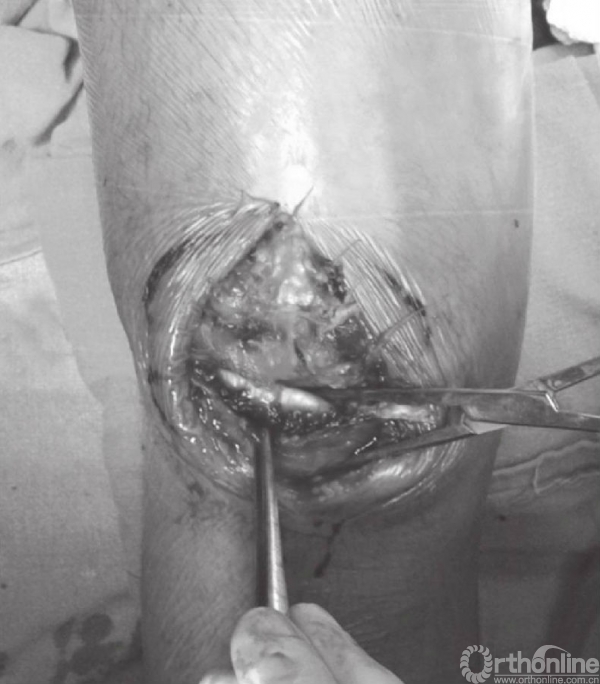

在张力带旋紧固定后,用钢丝剪剪除多余钢丝。突出的部分折弯后贴近髌骨上极放置(图15)。克氏针末端用折弯器折弯后尽量贴近髌骨表面。钢丝末端旋转后经股肌间隙埋入股四头肌腱(图16)。后期缝合肌间隙,可防止克氏针退出。克氏针远端在近髌骨处切断(图17)。用不可吸收线缝合撕裂的支持带(图18)。屈膝90°,以评估内固定的稳定性(图19)。

图18 在髌骨两侧用不可吸收缝线缝合撕裂的支持带